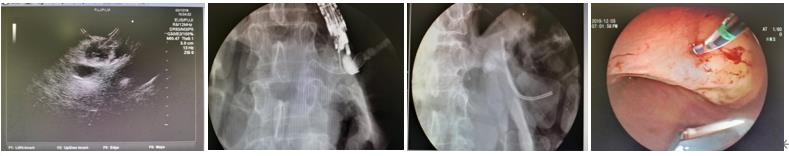

换用扇扫超声,胰腺体尾部胰管宽约0.6cm,选取胃体底交接小弯侧为穿刺点,避开血管,19G穿刺针成功进入胰管,应用双头导丝进入胰管,但无法满意进入体尾部胰管盘曲。后换用小丑导丝成功进入体尾部胰管。应用针刀打通及扩张穿刺路径,之后应用7Fr扩张探条进一步扩张穿刺路径,沿导丝置入7Fr×6cm胆道支架于胰管内(一侧位于胃底腔内),观察位置良好,吸气后退镜。

超声内镜引导下胰管穿刺引流术(EUS-PD)